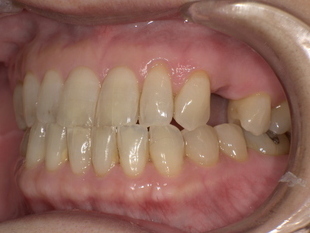

▼ 治療前

-

歯の欠損部の影響で口元がへこみ、老けた印象

バネ式の入れ歯では金具が見えてしまう

噛み合わせが不安定で、しっかり食べられない